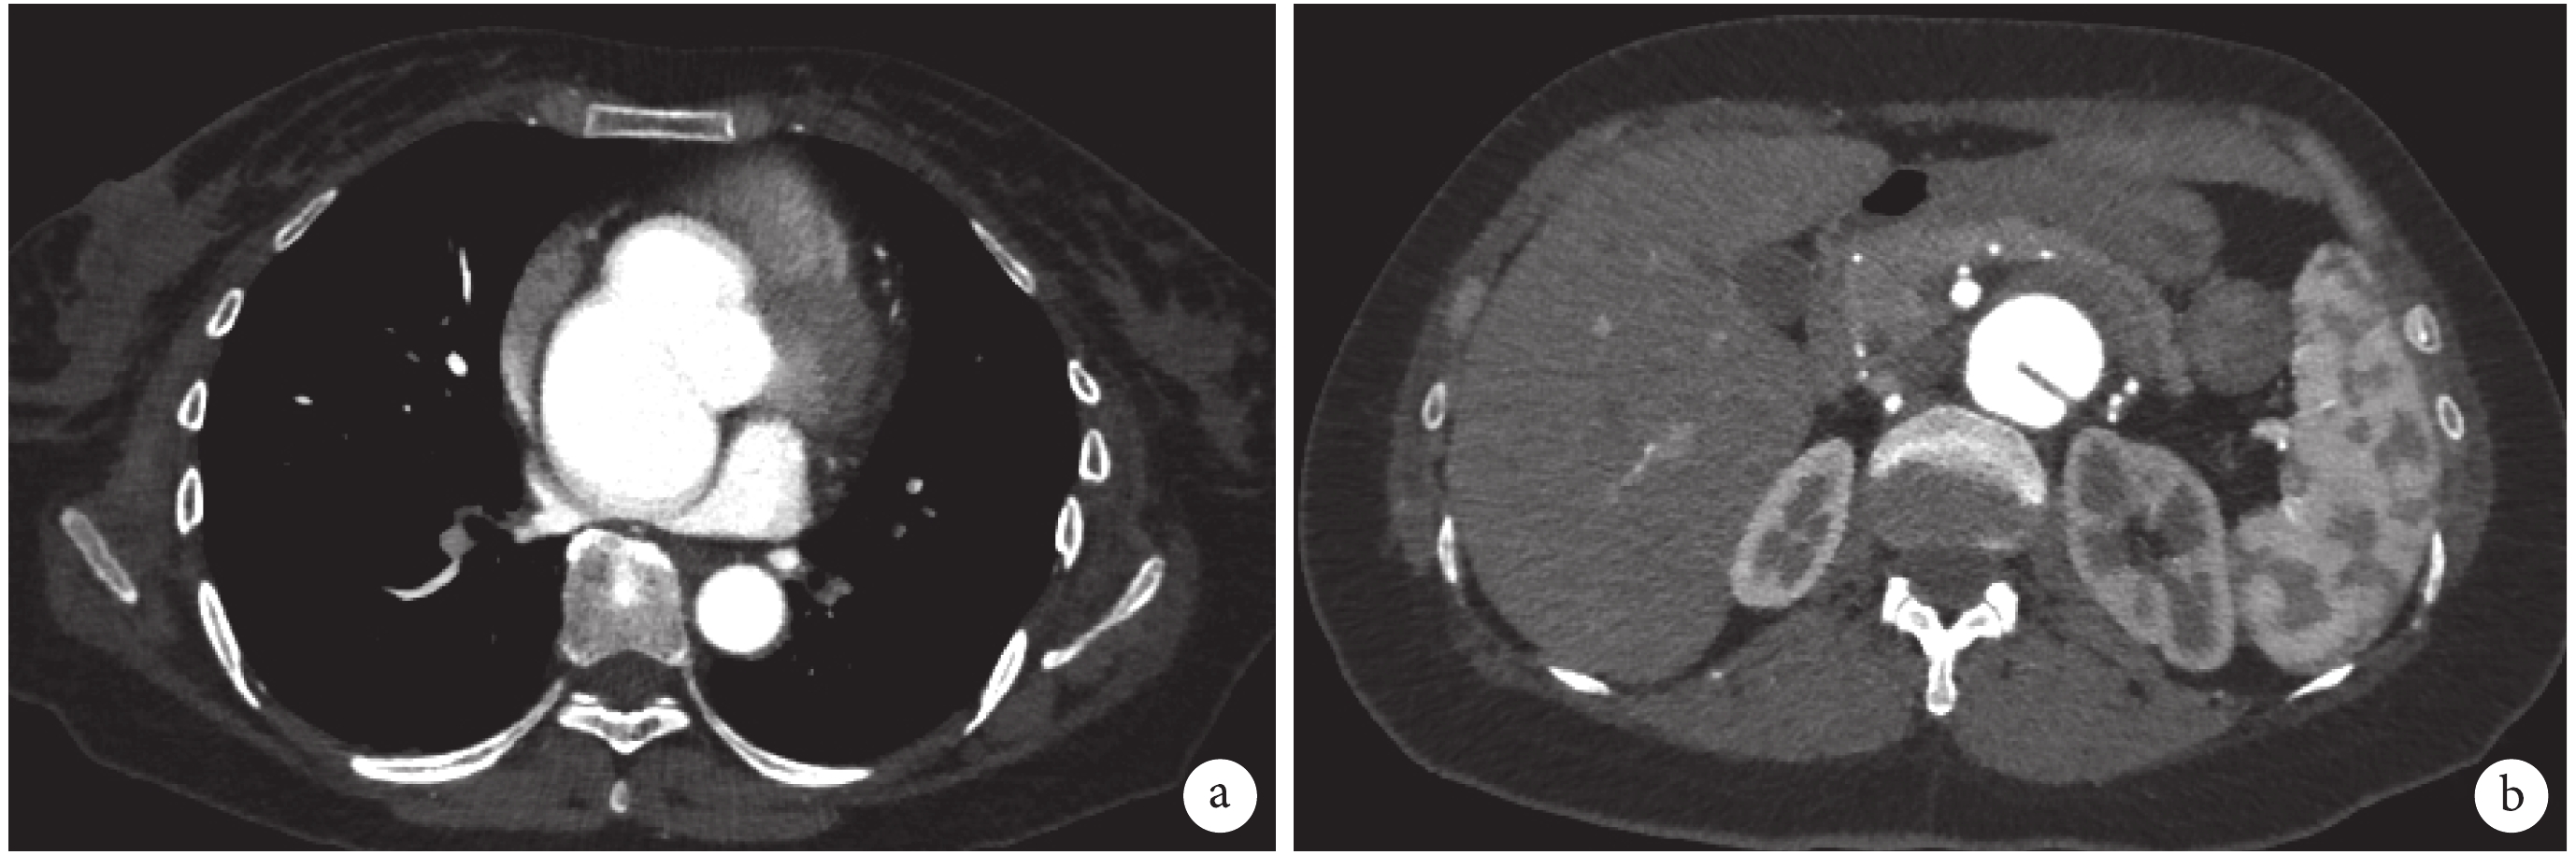

a:非對稱性主動脈竇瘤,無竇部擴張明顯,向下后方膨凸,左房受壓變形;b:腹主動脈夾層:腸系膜上動脈開口以遠,至雙側髂總動脈起始段主動脈腔可見內膜片影,呈雙腔結構

臨床資料 患者,女,37 歲,因“腹痛診斷腹主動脈夾層 1 個月伴胸悶 1 周”就診于我院。患者 1 個月前無明顯誘因出現陣發性腹痛,外院就診行 CT 檢查診斷為腹主動脈夾層,予以保守治療后好轉,未行胸部影像學檢查,故未能診斷主動脈竇部擴張。1 周前患者自覺胸悶,后背不舒服遂來就診。既往史和家族史均無特殊。體格檢查:身高 168 cm,體重 60 cm。血壓 128/80 mm Hg。心臟聽診可聞及主動脈舒張期雜音;腹主動脈未見搏動性腫塊。凝血功能檢查顯示 D-二聚體(D-dimer)2.13 μg/mL(正常<0.5 μg/mL),纖維蛋白降解產物(FDP)8.42 μg/mL(正常 0~5 μg/mL);其余檢驗無異常。超聲檢查提示主動脈瓣環內徑 25 mm,竇部前后徑 66 mm,升主動脈 37 mm,左室舒張期末內徑 55 mm,射血分數(EF)58%,主動脈瓣中量反流。增強 CT 顯示非對稱性主動脈竇瘤,無竇部擴張明顯,向下后方膨凸,左房受壓變形(圖 1a);腹主動脈夾層:腸系膜上動脈開口以遠,至雙側髂總動脈起始段主動脈腔可見內膜片影,呈雙腔結構(圖 1b)。腹主動脈近端直徑 17 mm,夾層累及最寬處為 39 mm。腹腔干及腸系膜上動脈顯影良好,未受累。左腎動脈起自假腔,右腎動脈一支起自真腔,一支起自假腔。雙腎灌注良好。3D 重建顯示全主動脈(圖 2a)和腹主動脈夾層(圖 2b)。基因檢測發現 FBN1 突變。患者被診斷為:馬凡綜合征(MFS),主動脈竇瘤,腹主動脈夾層。該患者行單純 Bentall 手術,腹主動脈夾層予以保守治療。術后病理顯示主動脈瓣粘液樣變性(圖 3a),主動脈壁囊性中層壞死(圖 3b)。患者出院后口服華法林,鈣通道阻滯劑,沙坦類(ARB)。每 3 個月進行一次隨訪。至 2019 年 6 月 24 日患者已恢復正常生活。